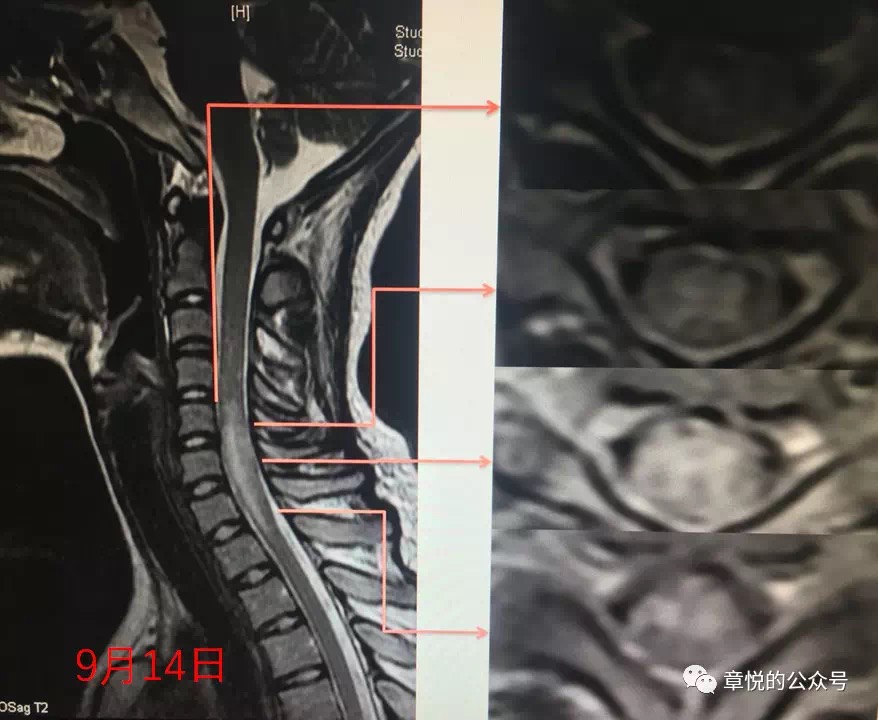

{有一次,急診室送來一位年僅20歲的女生。她在兩週前曾有腹瀉病史,發病當天下午洗澡時,突然出現了非常嚴重的頸背疼痛,隨後她開始感覺左側肢體麻木、右側下肢也逐漸變得無力,數小時內,症狀進一步擴展到右側身體,甚至出現排尿困難的症狀。另一家醫院的MRI檢查顯示,她的頸髓C5到C8位置出現了異常訊號,於是緊急轉到我們醫院。